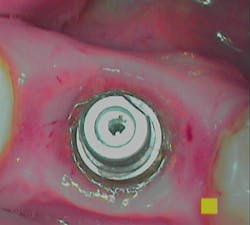

Assess the implant to diagnose its condition or health, including any hard- and soft-tissue deficiencies. Follow the Wingrove five-step implant assessment, which starts by assessing the tissue surrounding the implant, known as the perimucosal seal, for any inflammation that may be present. (3)

Note in the patient’s record whether any inflammation is visually present by using an intraoral camera if possible. Use the Gingival Index rating to assess the inflammation level on a scale of 1–3: mild, moderate, or severe (figures 1a–1c).